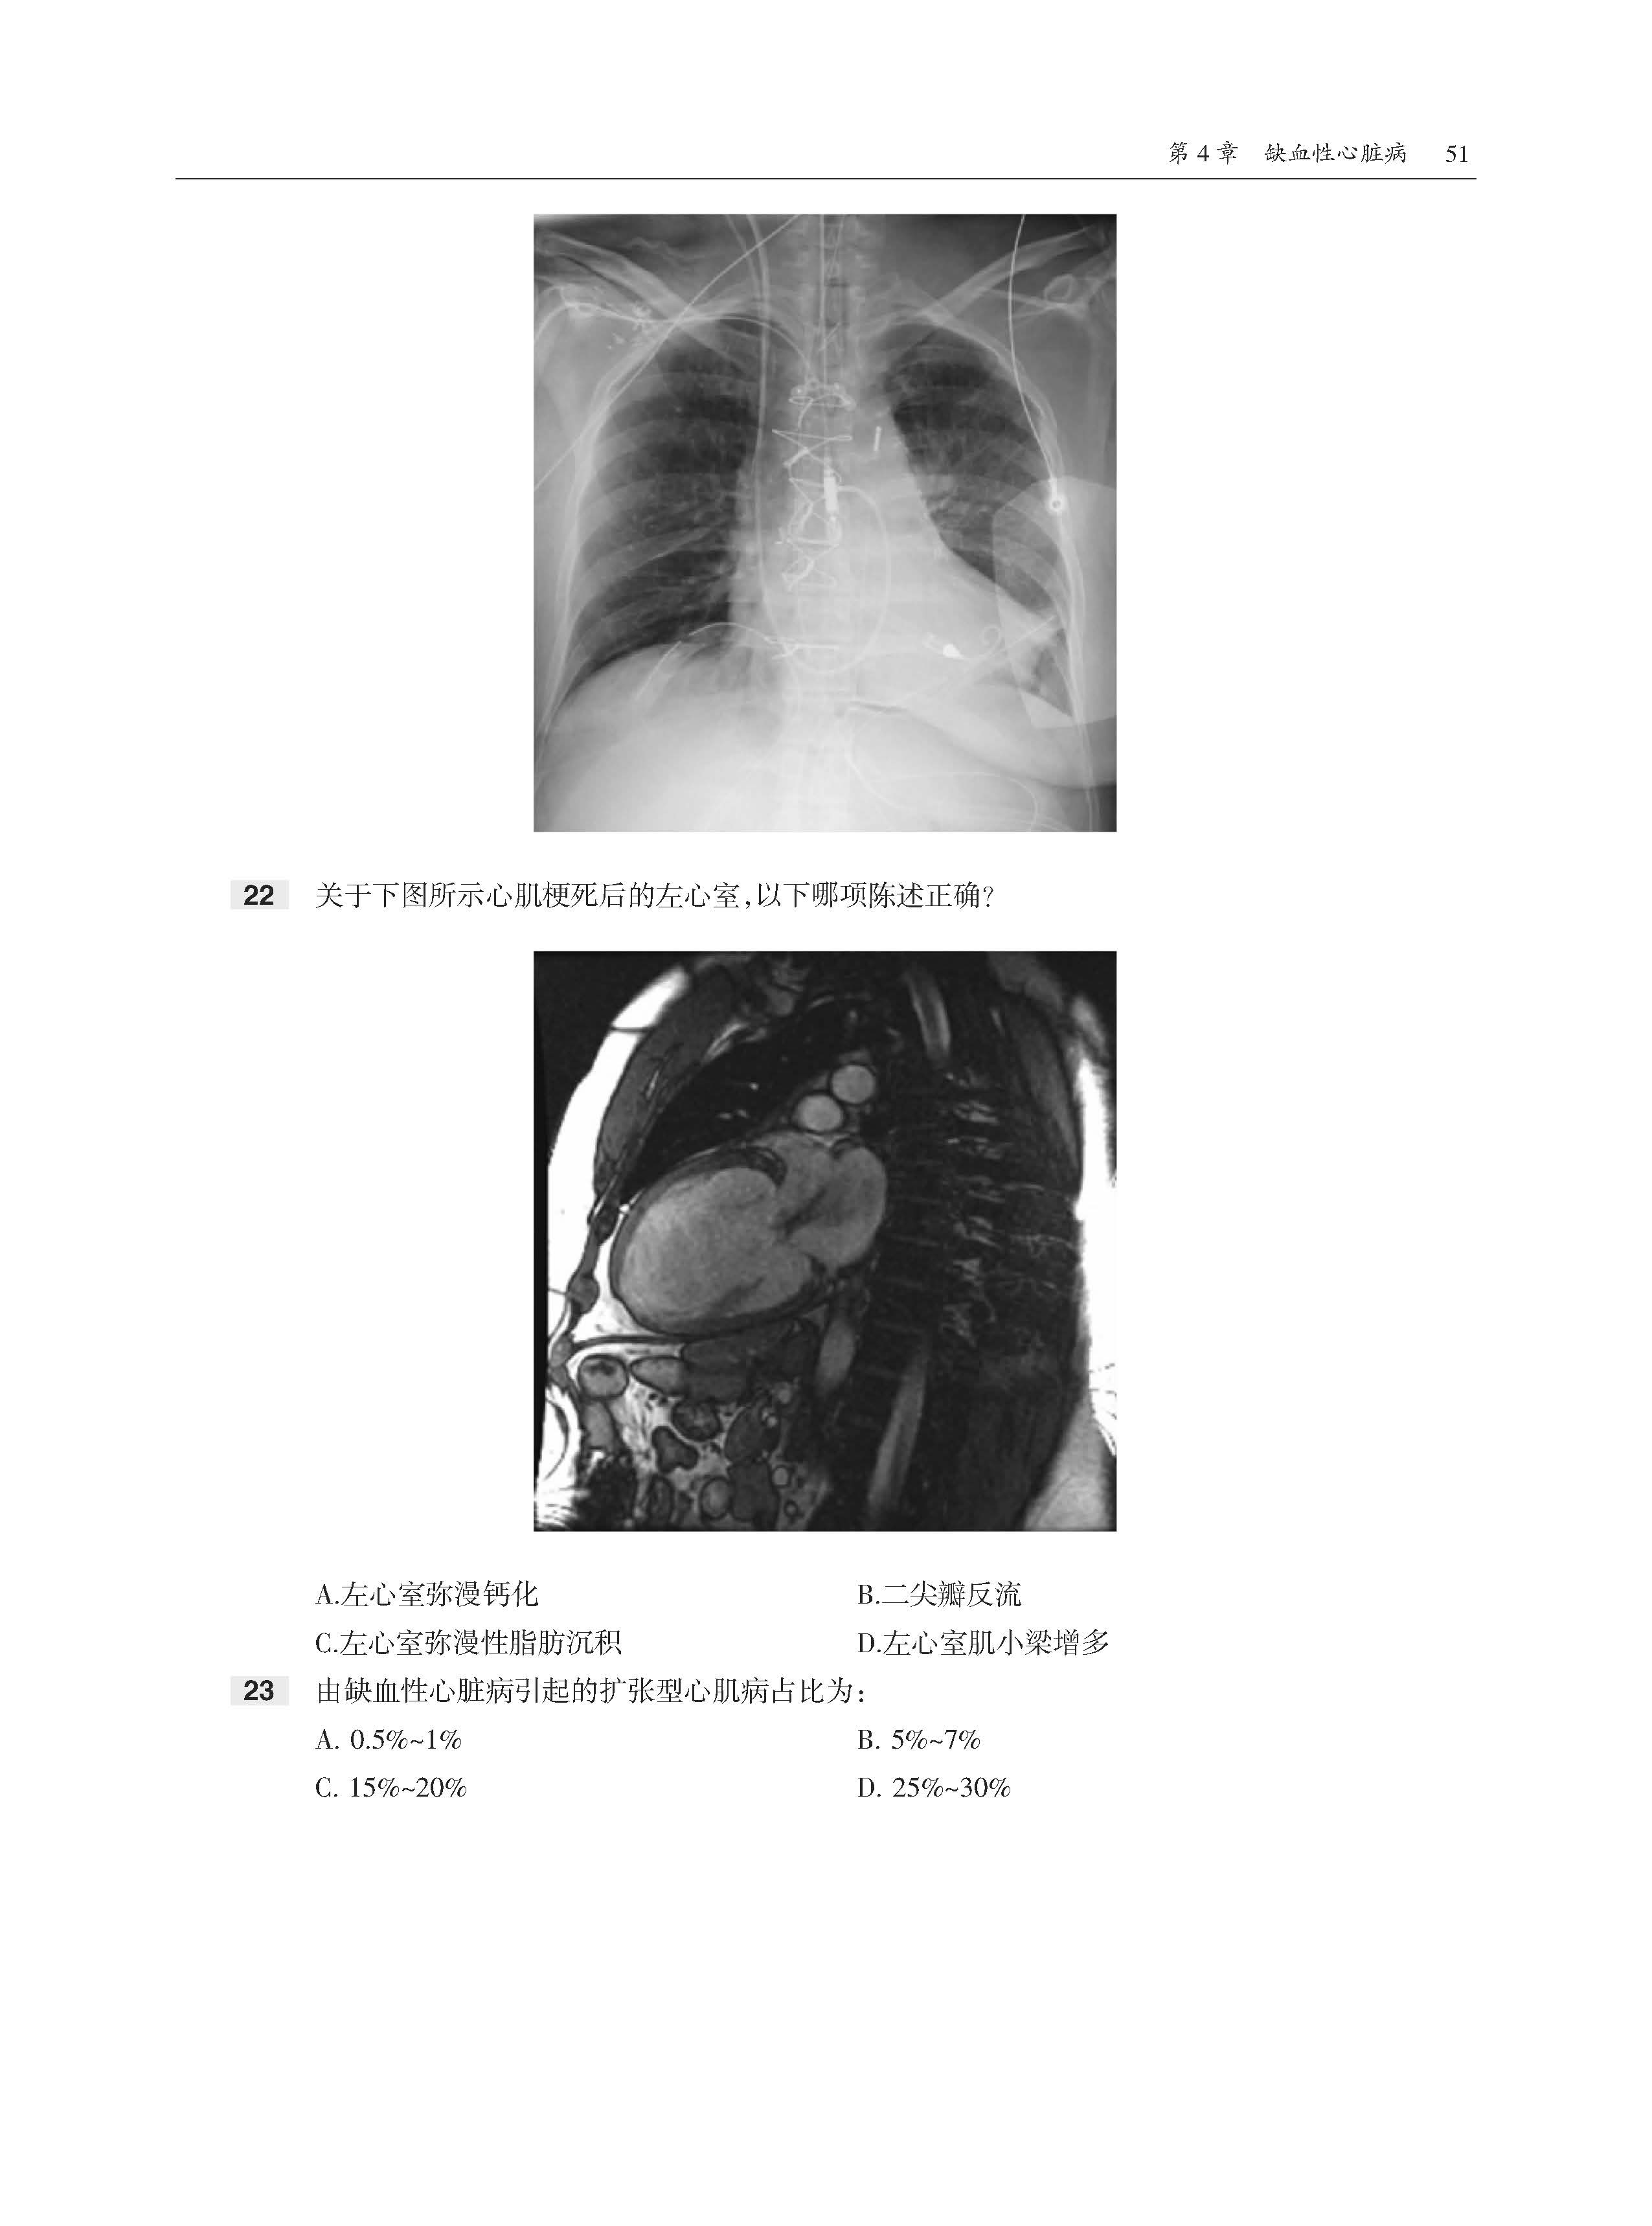

全书共11章内容,首先介绍了心脏放射成像基础和生理学基础,然后分别论述了缺血性心脏病、心肌病、心脏肿瘤、瓣膜病变、心脏周围病变、先天性心脏病、胸主动脉和大血管获得性病变,以及设备和术后表现。书中内容采用问答体例,各章开始均先给出患者影像图片和问题,供读者分析解答。在每章末尾给出问题答案,供读者参考。此书最大的特点是基于临床问题的多项选择题形式,每个选择题附有详细的解答,正确选项和错误选项均有详细的注释。该书全面回顾了心脏影像学的诊断要点,有助于读者理解和系统掌握心脏病变影像特点和诊断思路。

·300多道选择题,每道题都给出了答案、解析和相关参考文献。

·大量高清图像,直观展示病变。